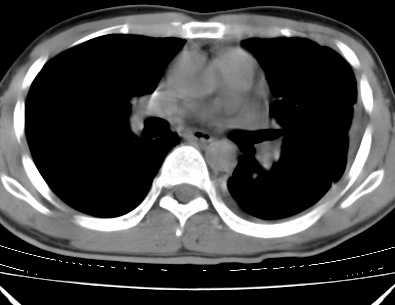

二周前患者无明显诱因出现咳嗽,多为刺激性干嗽,无咯血,伴心悸,低热,夜间无明显盗汗,消瘦明显

考虑:1、左侧中量胸腔积液伴左肺下叶肺膨胀不全、炎症。

2、心包积液。

1、左侧中量胸腔积液伴左肺下叶肺膨胀不全、。

左肺舌叶及下叶见斑片状,大片状高密度影并相应处胸膜及心包不规则增厚,左肺下叶膨胀不全。右肺未见异常,双肺段以上支气管通畅。纵隔左移,其内未见明显肿大淋巴结。左侧胸腔积液。

1.考虑:左肺化脓性炎症。2.左侧胸腔积液(中等量)。3.心包炎症。

炎性病变为主伴有肺的膨胀不全,伴胸腔积液.心包积液不好定建议超声纵隔淋巴结没看出.